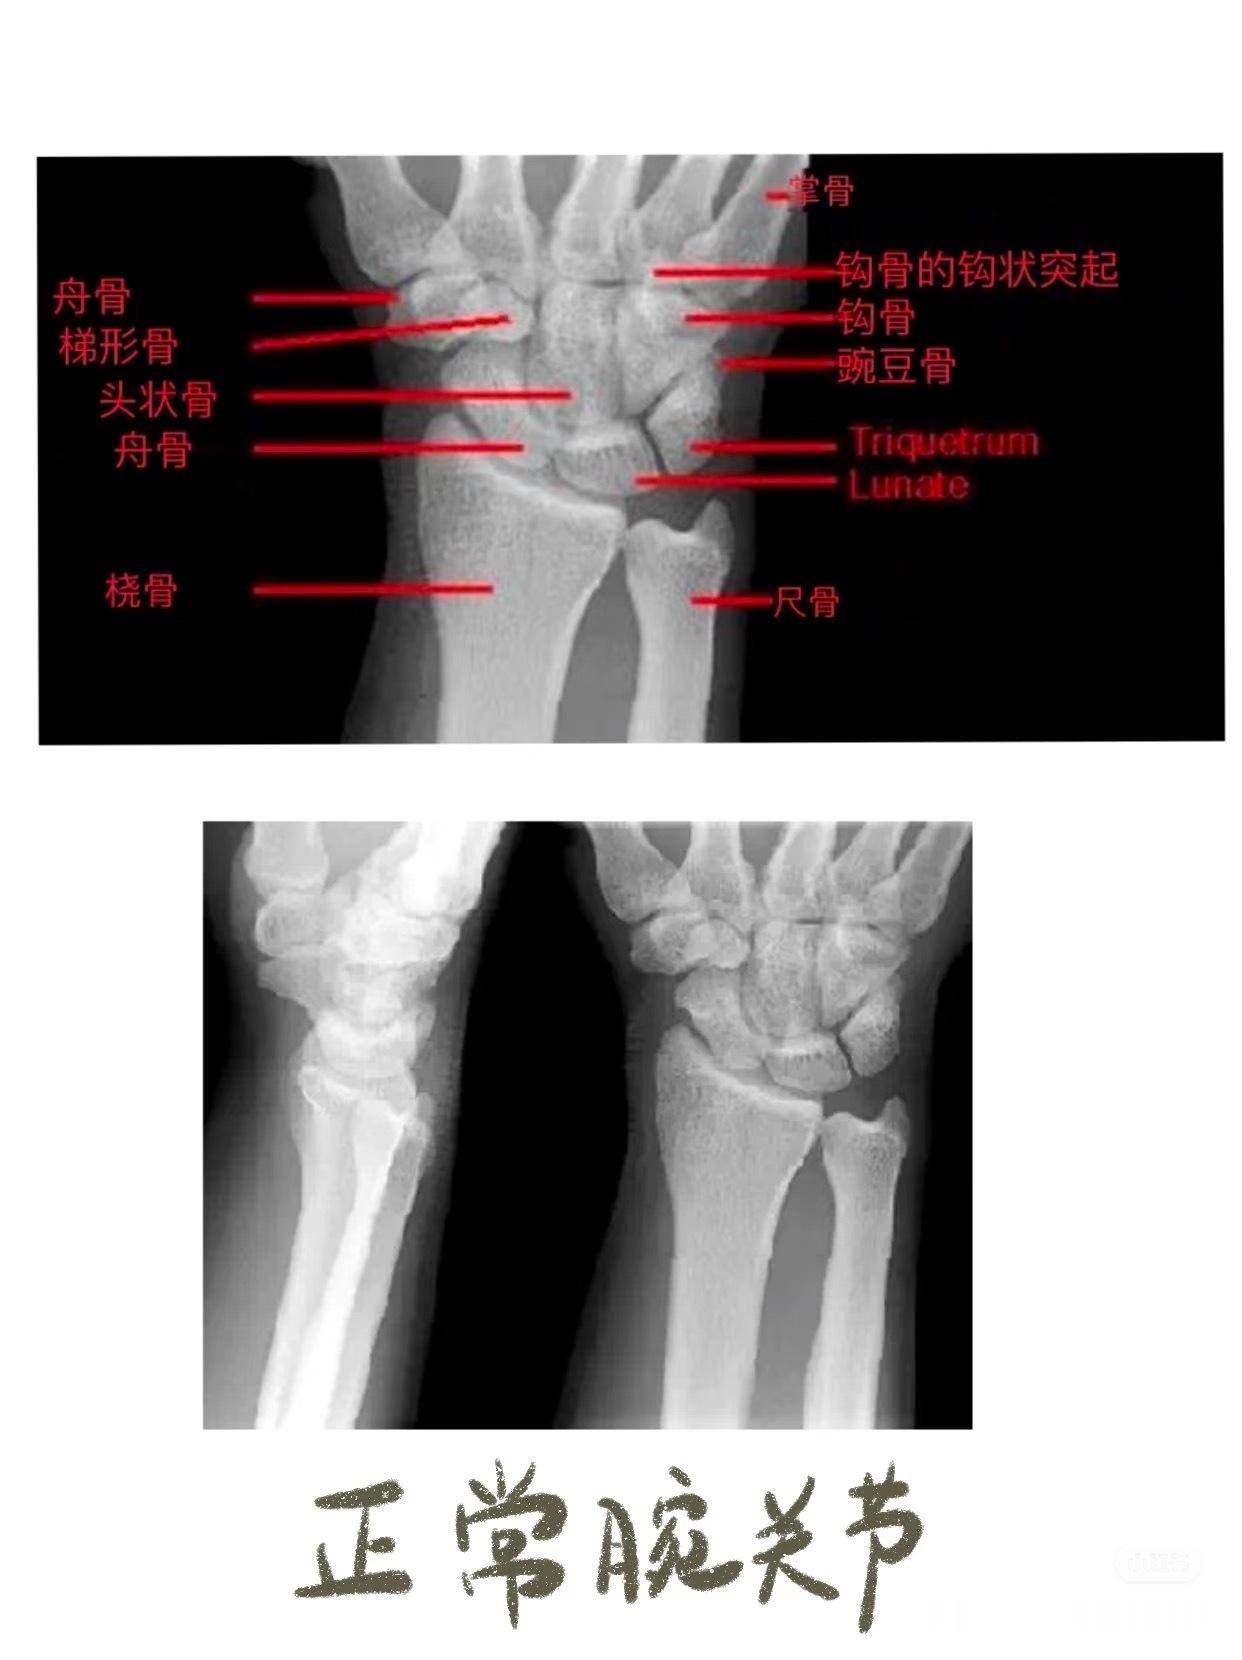

之前讲到影像学片子,膝盖和腰椎比较多,今天说些比较小众的——锁骨骨折,肘关节脱位,手部损伤等等👇🏻👇🏻【锁骨骨折的典型症状】01.疼痛与压痛——骨折部位出现持续性或阵发性剧烈疼痛。02.肿胀与皮下瘀斑——骨折后局部软组织损伤和出血,导致肿胀迅速出现,可能伴随皮下瘀血或青紫。03.畸形与异常活动——锁骨缩短、成角或旋转畸形,如骨折端上翘、隆起或凹陷。04. 活动受限——上肢抬举、伸展等功能受限,肩关节活动时疼痛加剧,甚至完全无法活动。05. 骨擦音/骨擦感——骨折断端摩擦时可触及异常活动或听到骨擦音,是骨折的典型体征。【肘关节脱位】01. 关节畸形——后脱位(最常见):尺骨鹰嘴向后突出,肘前窝饱满,前臂外观缩短,呈“靴状畸形”。——侧方脱位:肘关节向内或向外偏斜,形成肘内/外翻畸形。02. 肘后三角关系破坏 ——正常肘关节屈曲时,肱骨内/外上髁与尺骨鹰嘴构成等腰三角形;伸直时三点成一直线。——脱位后此关系完全失常。03. 弹性固定 ——关节被周围紧张韧带“锁扣”于半屈位,被动活动时有弹簧样阻力感。04. 骨性标志异常 ——后脱位时可触及肘后空虚感,尺骨鹰嘴异常隆起;——前脱位可触及肱骨远端。【手部骨折】拳击手骨折——握拳撞击——通常发生在第五掌骨(cr.骨科小龙笔记)大家如果还有关于骨折或者其他身体损伤的问题,都可以下方留言讨论